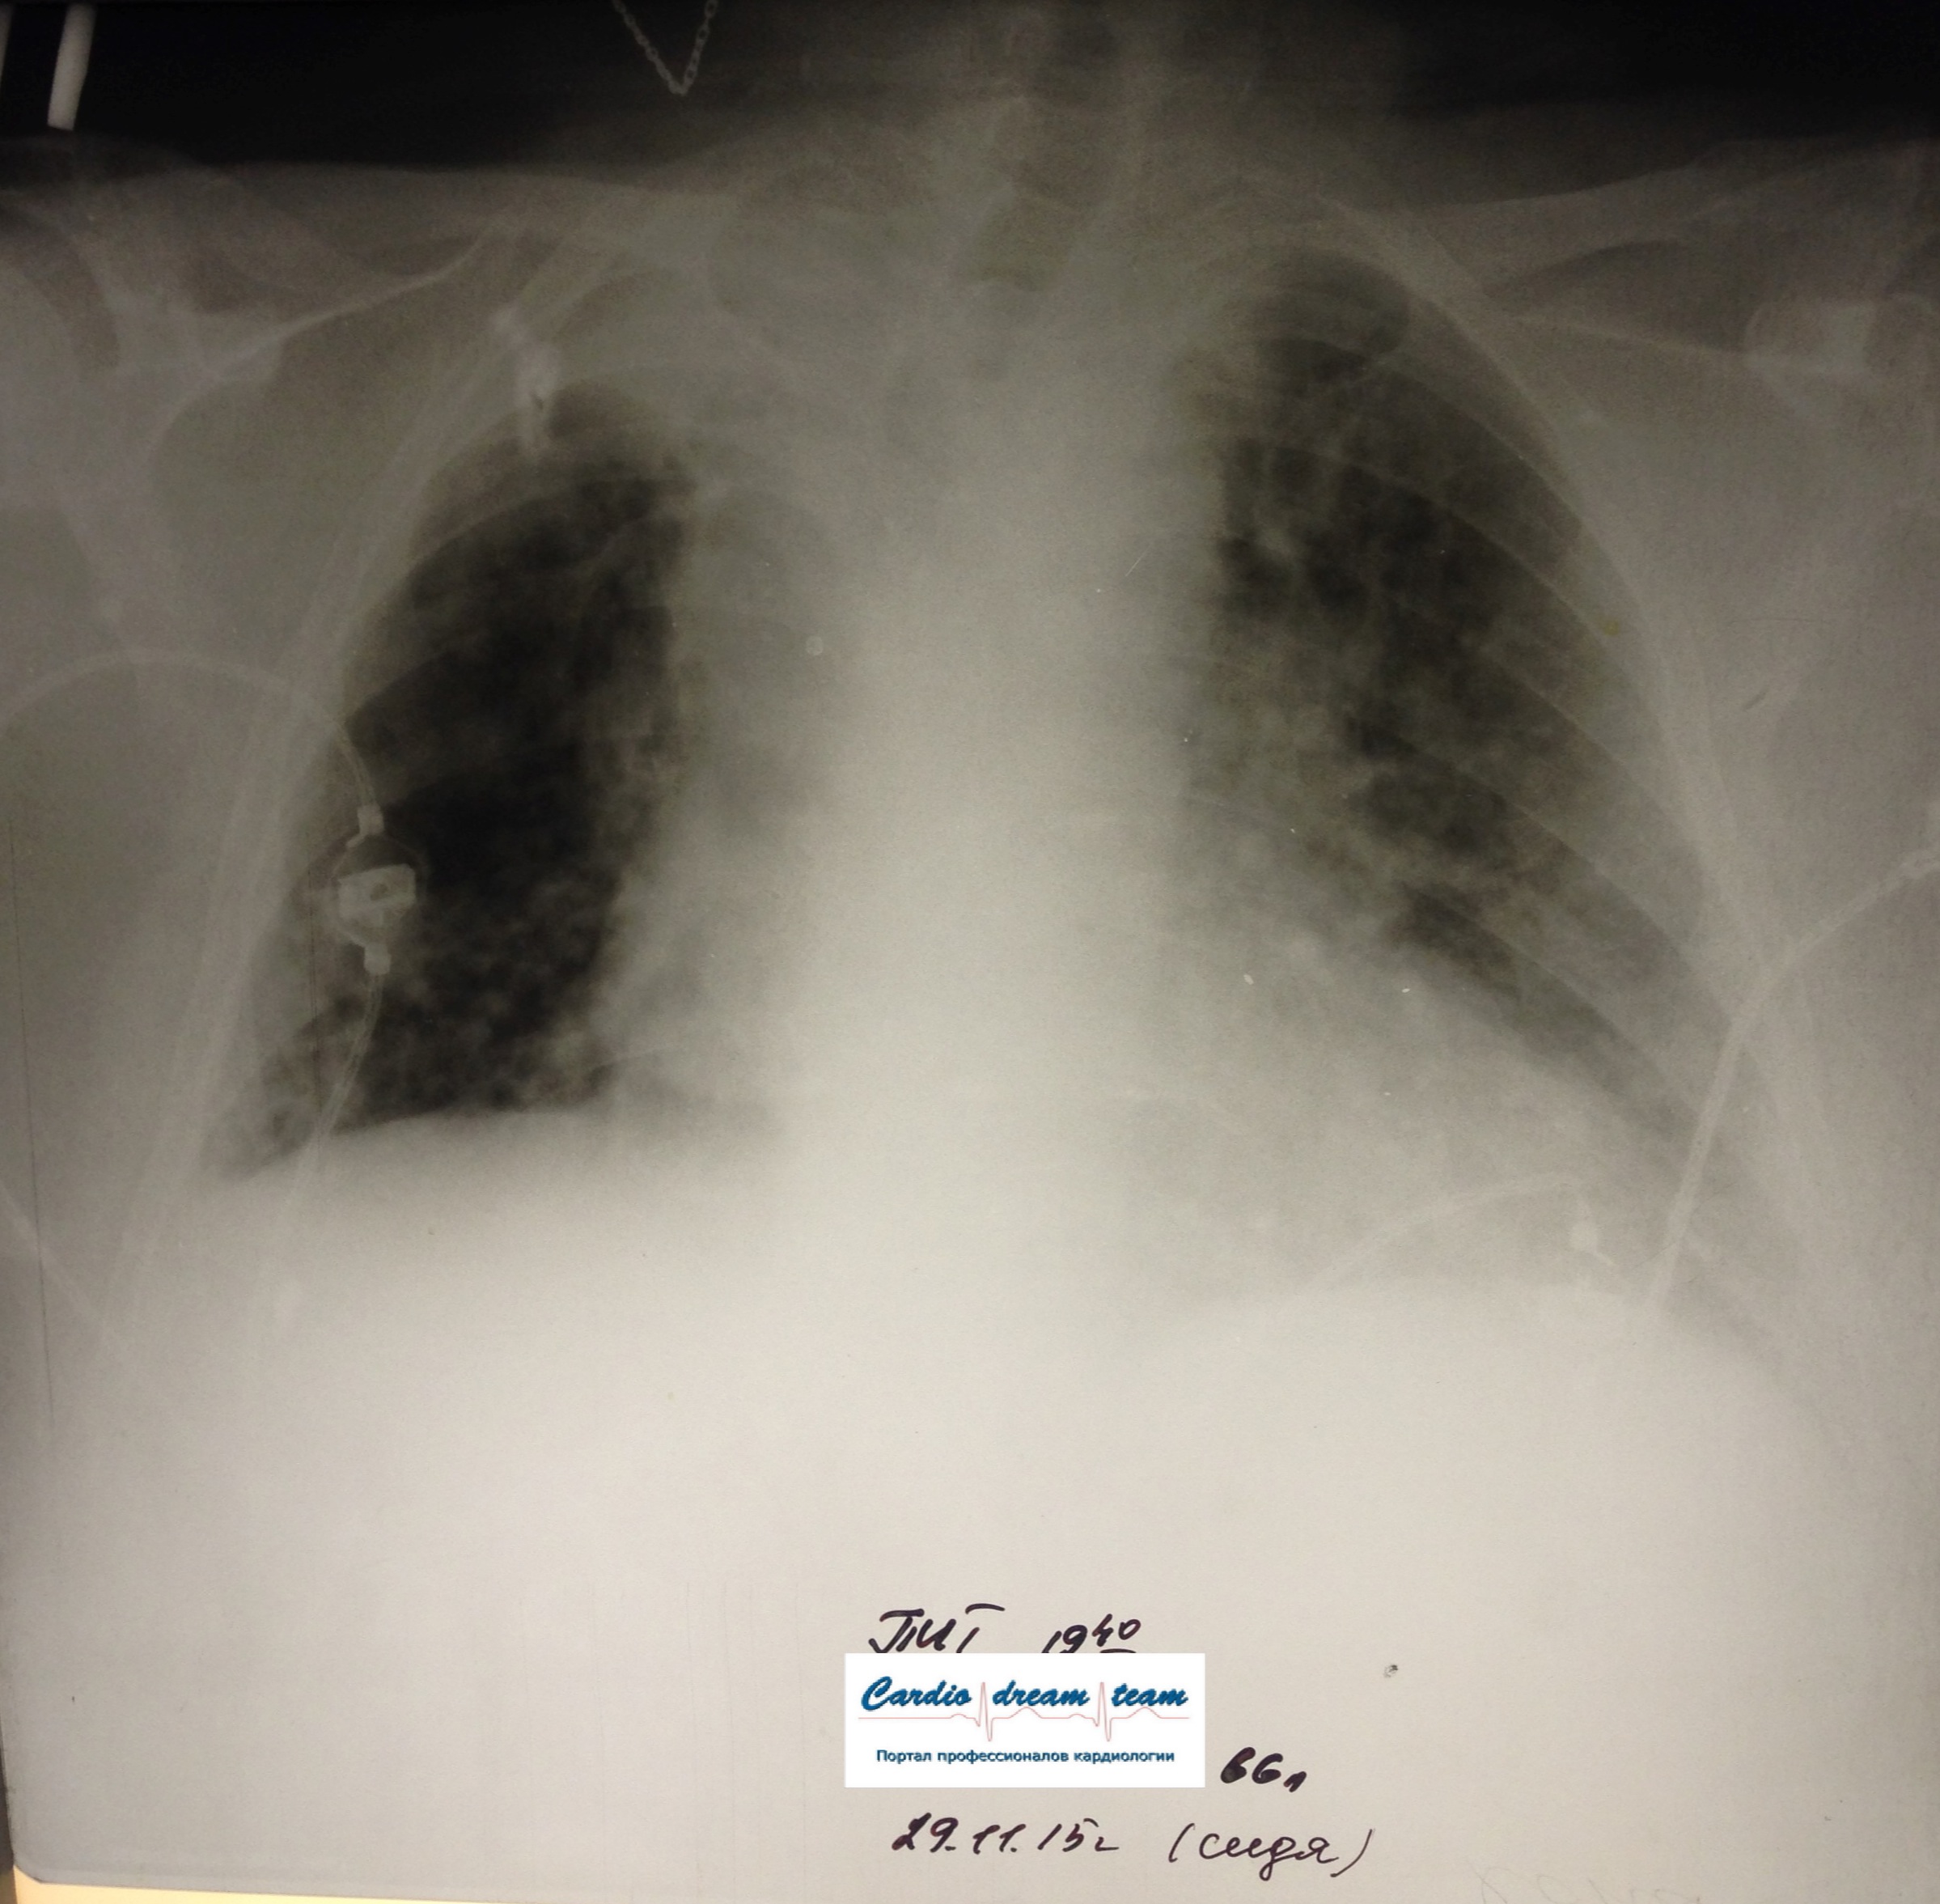

Не обсуждалась Дата 23-ИЮЛ-15 ОПИСАНИЕ: Проведена рентгенография органов грудной клетки в прямой проекции, положение лежа, условия ПИТ Легочные поля: неравномерно прозрачны за счет сосудистого обогащения, в базальных отделах с обеих сторон, отмечается сгущение легочного рисунка, за счет гиповентиляции, в плевральных полостях жидкость Легочный рисунок: Изменен по смешанному типу: обогащен за счет сосудистого компонента, деформирован за счет склероза. Корни: бесструктурны, расширены за счет сосудистого компонента, обогащены Синусы: определяется наличие жидкости по линии 5 ребра Сердце: широко лежит на диафрагме отмечается расширение границ сердечной тени влево, вправо экг-электроды. ЗАКЛЮЧЕНИЕ: Рентген-признаки 2-х стороннего гидроторакса с гиповентиляцией базальных сегментов.. Признаки застоя по МКК 2 степени (умеренно выраженный). Пневмосклероз. Р-признаки гипертрофии левого желудочка сердца. Склероз аорты.